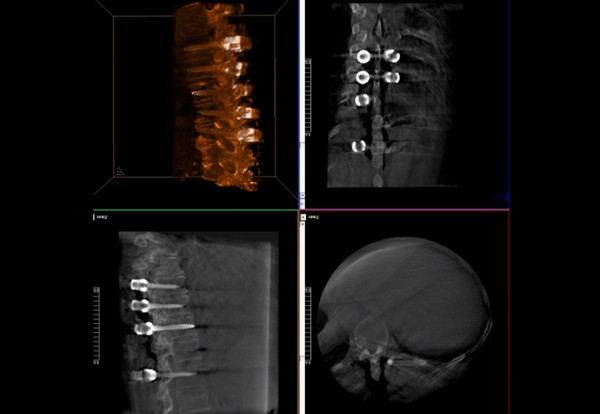

普愛醫療術中三維導航C臂快速生成橫斷面、矢狀面、冠狀面斷層圖像和三維立體圖像,方便醫生確認手術部位。C形臂的大平板帶來出色的顯示視野,可以更好的顯示手術部位全局情況,確保手術規劃及執行的準確性。

三維影像檢驗螺釘植入效果

一臺C形臂

二維三維影像 皆能完好呈現